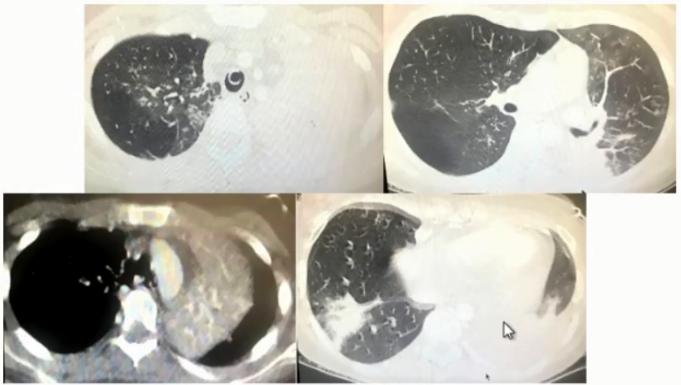

图1 患者的影像学以实变为主